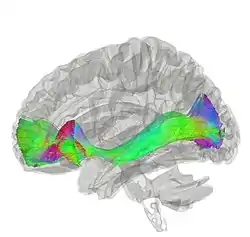

Tractography showing occipitofrontal fasciculus | |

The occipitofrontal fasciculus, also known as the fronto-occipital fasciculus, passes backward from the frontal lobe, along the lateral border of the caudate nucleus, and on the medial aspect of the corona radiata; its fibers radiate in a fan-like manner and pass into the occipital and temporal lobes lateral to the posterior and inferior cornua.